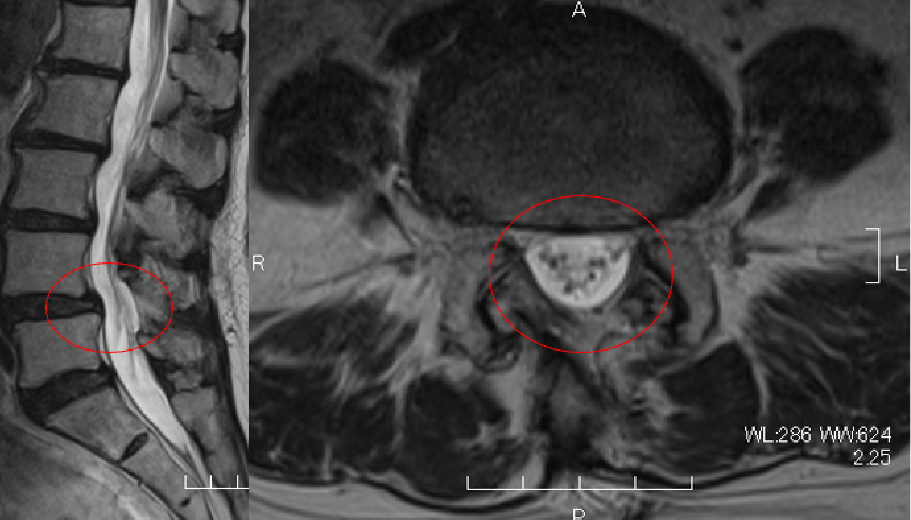

【第4/5腰椎部腰部脊柱管狭窄症に対する2双式内視鏡下椎弓切除(aFESS)の実例】

術前MRI:靱帯や骨が厚く変性し、

神経の通り道(脊柱管)が狭くなっています(丸印)。

術後MRI:厚くなった靱帯や骨が切除され、

脊柱管が広くなっています(丸印)。